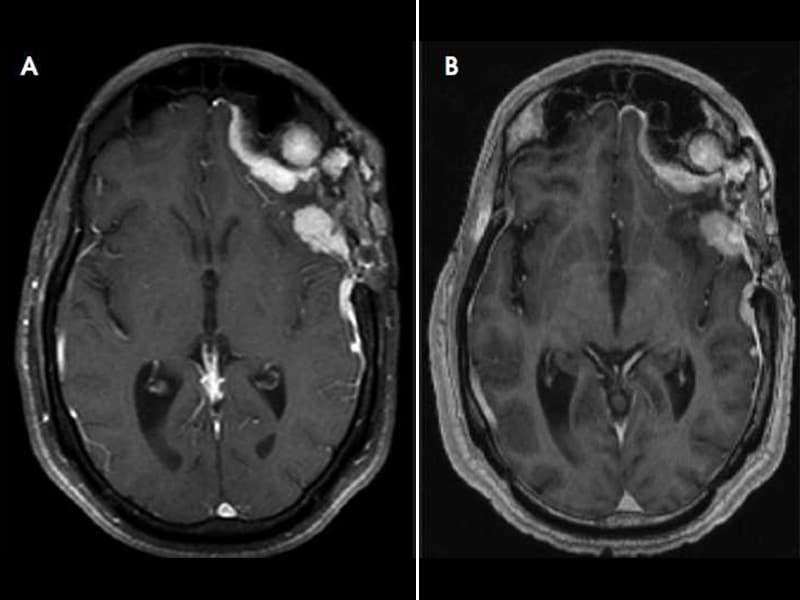

Κωνσταντίνος Χ. Δαβανέλος: Μηνιγγίωμα Εγκεφάλου.

Κωνσταντίνος Χ. Δαβανέλος: Μηνιγγίωμα Εγκεφάλου. from 3.bp.blogspot.com